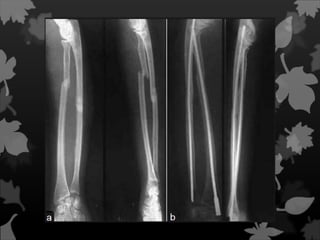

Fratura Espiral É quandoo traço de fratura encontra-se ao redor e através do osso.

Fratura oblíqua São decorrentes de lesõesque ocorrem com uma torção.

Fratura Segmentar Fratura dupla comduas linhas de fratura, que isola um segmento distinto do osso;

Fratura em Borboleta Fraturacom dois fragmentos de cada lado de um fragmento principal, separado em forma de cunha. Possui semelhança com asas de uma borboleta.

Fratura Estilhaçada. O ossoé esmigalhado em fragmentos finos e pontiagudos.